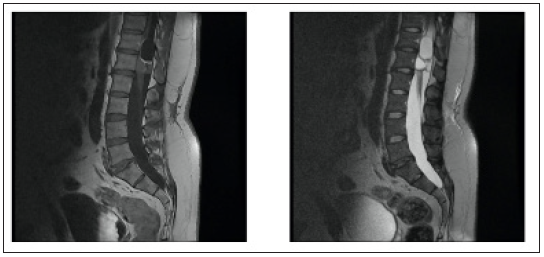

A 34-year-old male patient presented with a few months’ history of back pain. The patient had been treated with non-steroidal anti-inflammatory drugs (NSAIDs) for a few weeks in an outpatient clinic by a neurologist. Despite the treatment the back pain became constant and the patient started experiencing weakness in both legs while climbing stairs. The patient was referred for magnetic resonance imaging (MRI) of the thoracolumbar region (Figure 1 & 2). The MRI scan showed a multicompartmental heterogeneously enhanced intramedullary lesion located along Th12 and L1 vertebral bodies. A computed tomography angiography scan was also conducted and revealed neither spinal dysraphism, nor pathological vascular nidus. The patient was admitted to the Department of Neurosurgery in our hospital with spastic lower paraparesis (3 out of 5 on the muscle strength scale), bilateral positive Babinski sign, bilateral hypoesthesia below L1 dermatome, proprioceptive dysfunction in the lower extremities. Surgical treatment was suggested aiming for neural decompression, histologic verification and resection of the lesion. Laminectomies of Th12, L1 and partially on Th11 and L2 were conducted. Motor evoked potentials (MEPs) were monitored during the operation (Figure 3). The tumor was partially removed due to its adherence to the surrounding spinal cord and temporary deterioration of MEPs during surgical resection (Figure 4). The dura mater was closed with a watertight running suture and sealed with autologous fibrin glue. The histological examination revealed a mature teratoma (Figure 5). The patient had an uneventful postoperative period and was ambulating independently/muscle strength 5 out of 5/ on the 7th postoperative day. Control MRI was conducted 1 month postoperatively (Figure 6).

Figure 2: preoperative sagittal reconstructions of T1-weighted MR-images with contrast enhancement and T2 weighted MR-images of the lumber spine region. An intramedullary lesion with multiple cysts is observed end considerable compression of tbc medulla.